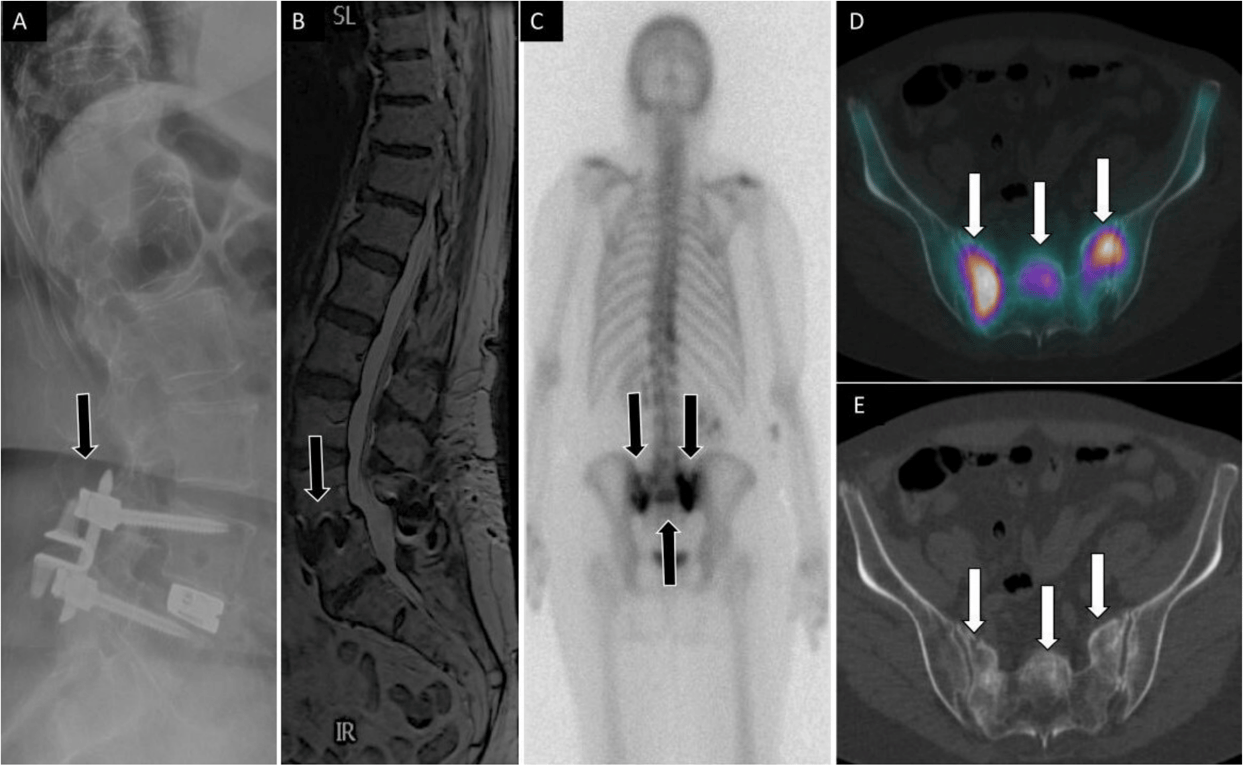

71-year-old woman with low back, buttock, and bilateral leg pain. Lateral (A) spine radiograph shows L4 to L5 instrumentation with prior interspinous spacer and unilateral pedicle screws with interbody device (arrow) without evidence of complications. Lumbar spine T2 sagittal magnetic resonance image (B) shows no central canal stenosis, also seen on axial (not displayed) and metal artifact at L4 to L5 (arrow) related to instrumentation. Posterior planar 99mTc-MDP bone scan (C) and axial fused single photon emission computed tomography with computed tomography (D) images show H-shaped radiotracer uptake within the sacrum, with associated sclerotic changes on computed tomography (E), compatible with sacral insufficiency fracture.